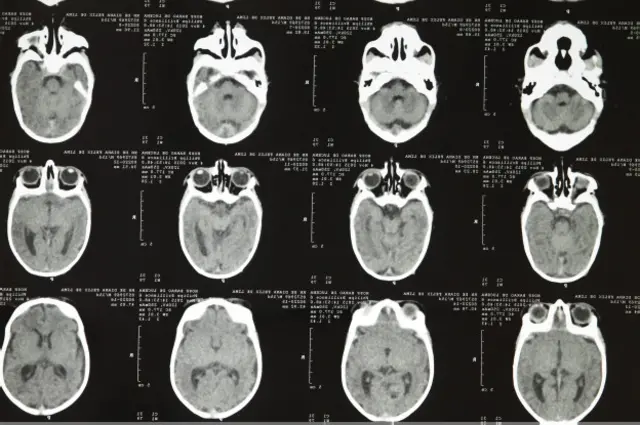

Cicatrizes no cérebro

A tomografia é a 'foto' do que aconteceu com o cérebro. Quando ocorre um processo de infecção, que é o que suspeitamos – geralmente entre o primeiro e o quarto mês de gestação –, o agente causador da infecção provoca um processo inflamatório que deixa cicatrizes no cérebro do bebê, que são as calcificações.

É como se essas calcificações – que podem ser maiores ou menores e estar em vários lugares do órgão – prendessem o cérebro. Aquelas áreas estão mortas, calcificadas. O cérebro não consegue crescer bem, cresce desorganizadamente, e outros problemas em sua estrutura aparecem. Quanto mais calcificações, mais desorganizado é este crescimento.

Estamos vendo tomografias muito alteradas, com calcificações extensas. Mas pode haver áreas do cérebro mais afetadas que outras. Cada criança vai ter um tipo de comprometimento a depender de como seu cérebro foi atingido.

Por isso, a criança precisa ser acompanhada por um neurologista por toda a vida. As que têm sequelas mais importantes podem ter convulsões de difícil controle, precisam tomar medicações específicas.

De qualquer forma, elas terão algum grau de comprometimento, mesmo que seja menor. Também podem ter coisas graves, como não falar, não andar e ter todo o desenvolvimento psicomotor alterado.

Quanto menor for perímetro cefálico, já entendemos que mais lesões aconteceram, que o cérebro foi atingido precocemente e não conseguiu crescer. Temos muitas crianças com a cabeça bem pequena: 27 cm, 28 cm, 29 cm. Ainda não temos todos os exames, mas pela nossa observação, a maioria parece estar entre 28 cm e 30 cm.

"O que estamos vendo aqui são casos em que os bebês foram formados corretamente, mas houve uma infecção no período de gravidez. As tomografias mostram características de processos infecciosos", afirmou.